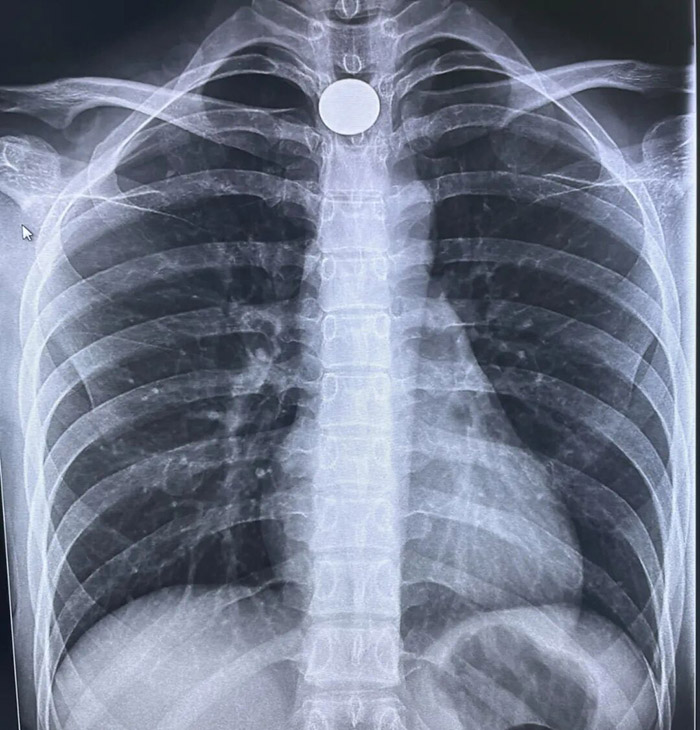

被送至医院时,乐乐已出现典型的吸气性呼吸困难,胸骨上窝、锁骨上窝可见明显凹陷——这是气道梗阻的危险信号。我院耳鼻喉科主任高巍接诊后立即判断:“异物很可能卡在食道入口,呛咳已引发喉部水肿,必须马上处理,否则随时可能窒息!”

精准施救 微创取物 手术采用“直达喉镜引导下食道镜异物取出术”,以最大程度减少对患儿食道的损伤。麻醉生效后,医生借助支撑喉镜缓缓探入,在高清视野下精准锁定——一枚硬币正横卡于食道入口狭窄处,边缘已压迫黏膜。

“稳住钳子,慢慢旋转……”高巍主任亲自操作,用特制异物钳稳稳钳住硬币边缘,经轻柔旋转调整角度后,一次性将硬币完整取出。整个过程干脆利落,仅耗时15分钟。硬币取出的瞬间,乐乐的呼吸立即变得通畅,面色也逐渐恢复红润。术后检查显示,孩子食道黏膜无明显损伤,当日即可进食少量流质食物。